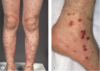

Purpura d'henoch Scholein

Cause de vasculite leucocytoclasique

Vasculite des petits vaisseaux

117

Vasculite des petits vaisseaux